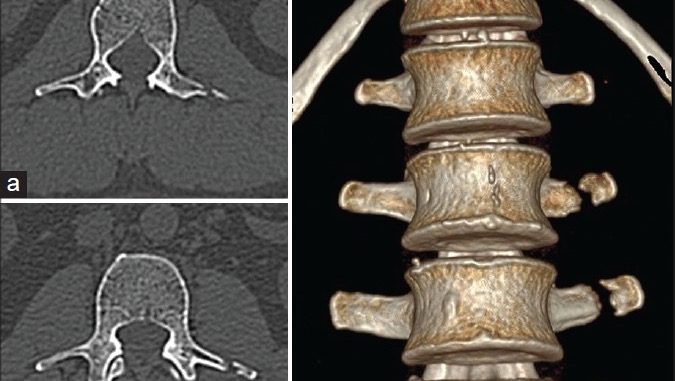

This is for our friend Hugo who is the most adventurous, free spirited, brave and loving. He was involved in an accident in San Francisco while he was jogging by Golden Gate Bridge. The impact that took place between him and someone on a bicycle was beyond belief- following time spent in the ER, incredible pain in his back that got fractured, pain in the legs, and 2 months of mandatory rest while he cannot get out of bed. In addition to all the injuries, he cannot work, and cannot get disability through work. The other person involved is nowhere to be found and this is where we, his friends and family, jump in to add a little relief.